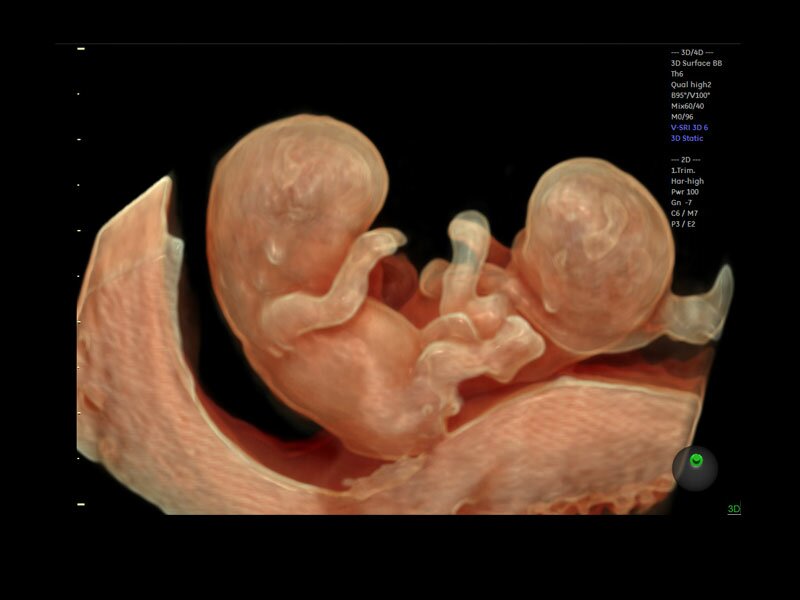

• Программа объемной визуализации плода классический HD-Live + расширенный пакет Hdlive Silhouette и Studio:

• HDlive Studio - три независимых источника освещения с регулировкой интенсивности

Объемное сканирование Voluson — 3D/4D вашей мечты

Объемное УЗИ на Voluson E10 — это не просто потрясающе красивая картинка, это ценный инструмент получения дополнительной информации при обследовании женщин.

Voluson E10 поддерживает инновационные технологии формирования изображений — HDlive Silhouette и HDlive Flow, которые позволяют увидеть мельчайшие детали. Алгоритм SonoRenderlive упрощает рабочий процесс и дает возможность реконструировать изображение поверхностей, определяя область перехода между тканью и жидкостью.

Инновационная технология визуализации HDlive обеспечивает получение реалистических изображений за счет эффекта объемного зрения, повышая достоверность клинической оценки. Теперь режим HDlive дополняют две новые функции: